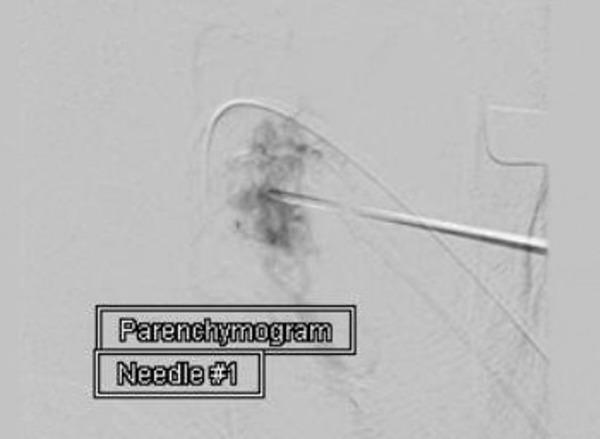

Preoperative embolization via transarterial route is an acceptable adjunct to the treatment of carotid body tumors (CBT). Direct tumor puncture for embolization has been previously described as a safe and feasible option. We revisit this technique and present our initial experience treating CBT via direct puncture. We identified six patients that underwent preoperative embolization of CBT using a direct puncture technique embolized with Onyx (EV3 Micro Therapeutics Inc., Irvine, CA, USA). After defining the angioarchitecture via digital subtraction angiography, the tumor was targeted with Onyx. Using a 21-gauge needle, the tumor was punctured using a fluoroscopic road mask. There were no immediate post-procedural complications following embolization. All patients underwent definitive resection within 24 hours. During surgery, the embolization material did not affect surgical maneuvers. In addition, the estimated blood loss was noted to average 50 ml.  Although early in our experience, direct percutaneous embolization of CBT appears to be a reproducible and well-tolerated endovascular treatment option. Overall, the reported body of evidence available confirms the safety and efficacy of direct intralesional embolization with Onyx.

经动脉途径的术前栓塞是治疗颈动脉体瘤(CBT)的一种可接受的辅助方法。先前已描述直接肿瘤穿刺栓塞是一种安全可行的选择。我们重新审视了这项技术,并介绍了我们通过直接穿刺治疗CBT的初步经验。我们确定了6例使用直接穿刺技术并用Onyx(美国加利福尼亚州欧文市EV3 Micro Therapeutics公司)栓塞进行CBT术前栓塞的患者。通过数字减影血管造影确定血管结构后,用Onyx对肿瘤进行靶向栓塞。使用21号针,在荧光透视路图引导下穿刺肿瘤。栓塞后无即刻术后并发症。所有患者均在24小时内接受了根治性切除。手术过程中,栓塞材料未影响手术操作。此外,估计平均失血量为50毫升。尽管这只是我们的初步经验,但CBT的直接经皮栓塞似乎是一种可重复且耐受性良好的血管内治疗选择。总体而言,现有报道的证据证实了使用Onyx进行直接瘤内栓塞的安全性和有效性。